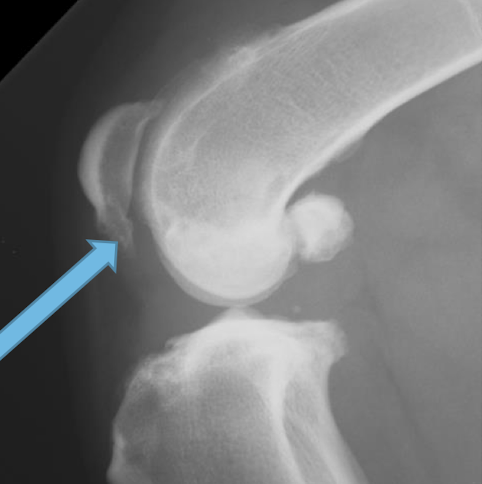

What is the image pointing to?

osteophytes